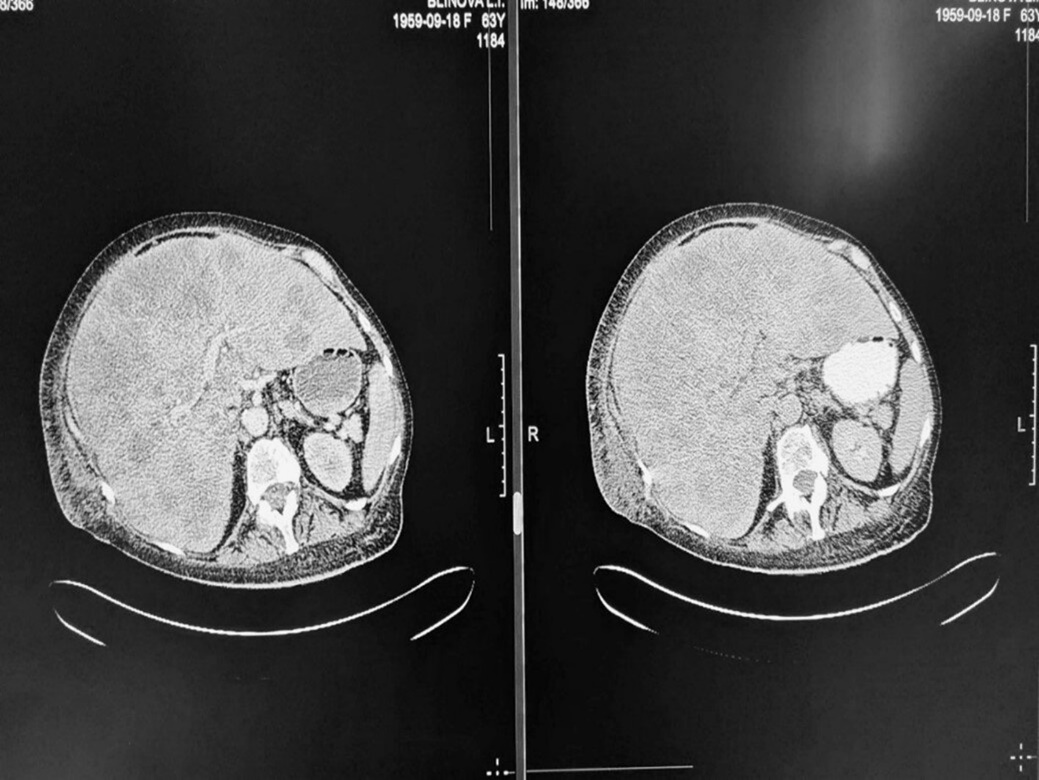

На сериях мультиспиральной компьютерной томографии печень расположена типично, увеличена в размерах: переднезадний размер до 8,9 см, косой каудальный размер – до 16,2 см для левой доли, а для правой доли – переднезадний размер – до 21,4 см и косой каудальный размер – до 25,0 см. Контуры четкие, неровные, а края закруглены. Структура паренхимы неоднородная из-за диффузного поражения гиподенсивными разнокалиберными очагами. Некоторые из них сливаются, образуя перегородки различной толщины. Большинство образований имеют четкие ровные контуры. В единичных образованиях отмечаются гиперденсивные включения. Накопление контрастного вещества в непораженной части паренхимы равномерное, но в гиподенсивных очагах контраст не накапливается. Протоки желчи и вены расширены нормально. Селезенка расположена и размерами соответствует норме. Воротные и селезеночные вены не расширены. В брюшной полости обнаружена свободная жидкость тонкой полоской парапеченочно по латеральной поверхности и в дугласовом пространстве.

Мультиспиральная компьютерная томография показывает увеличение печени с диффузным образованием кист, что, вероятно, соответствует поликистозу печени. Несколько из этих кист имеют осложнения, такие как кровоизлияния в стенки и контурное контрастирование. Также отмечается увеличение лимфоузлов в воротах печени, небольшое наличие жидкости в брюшной полости и плевральный выпот с обеих сторон грудной клетки (рис. 1).

Рис. 1. МСКТ-картина поражения печени